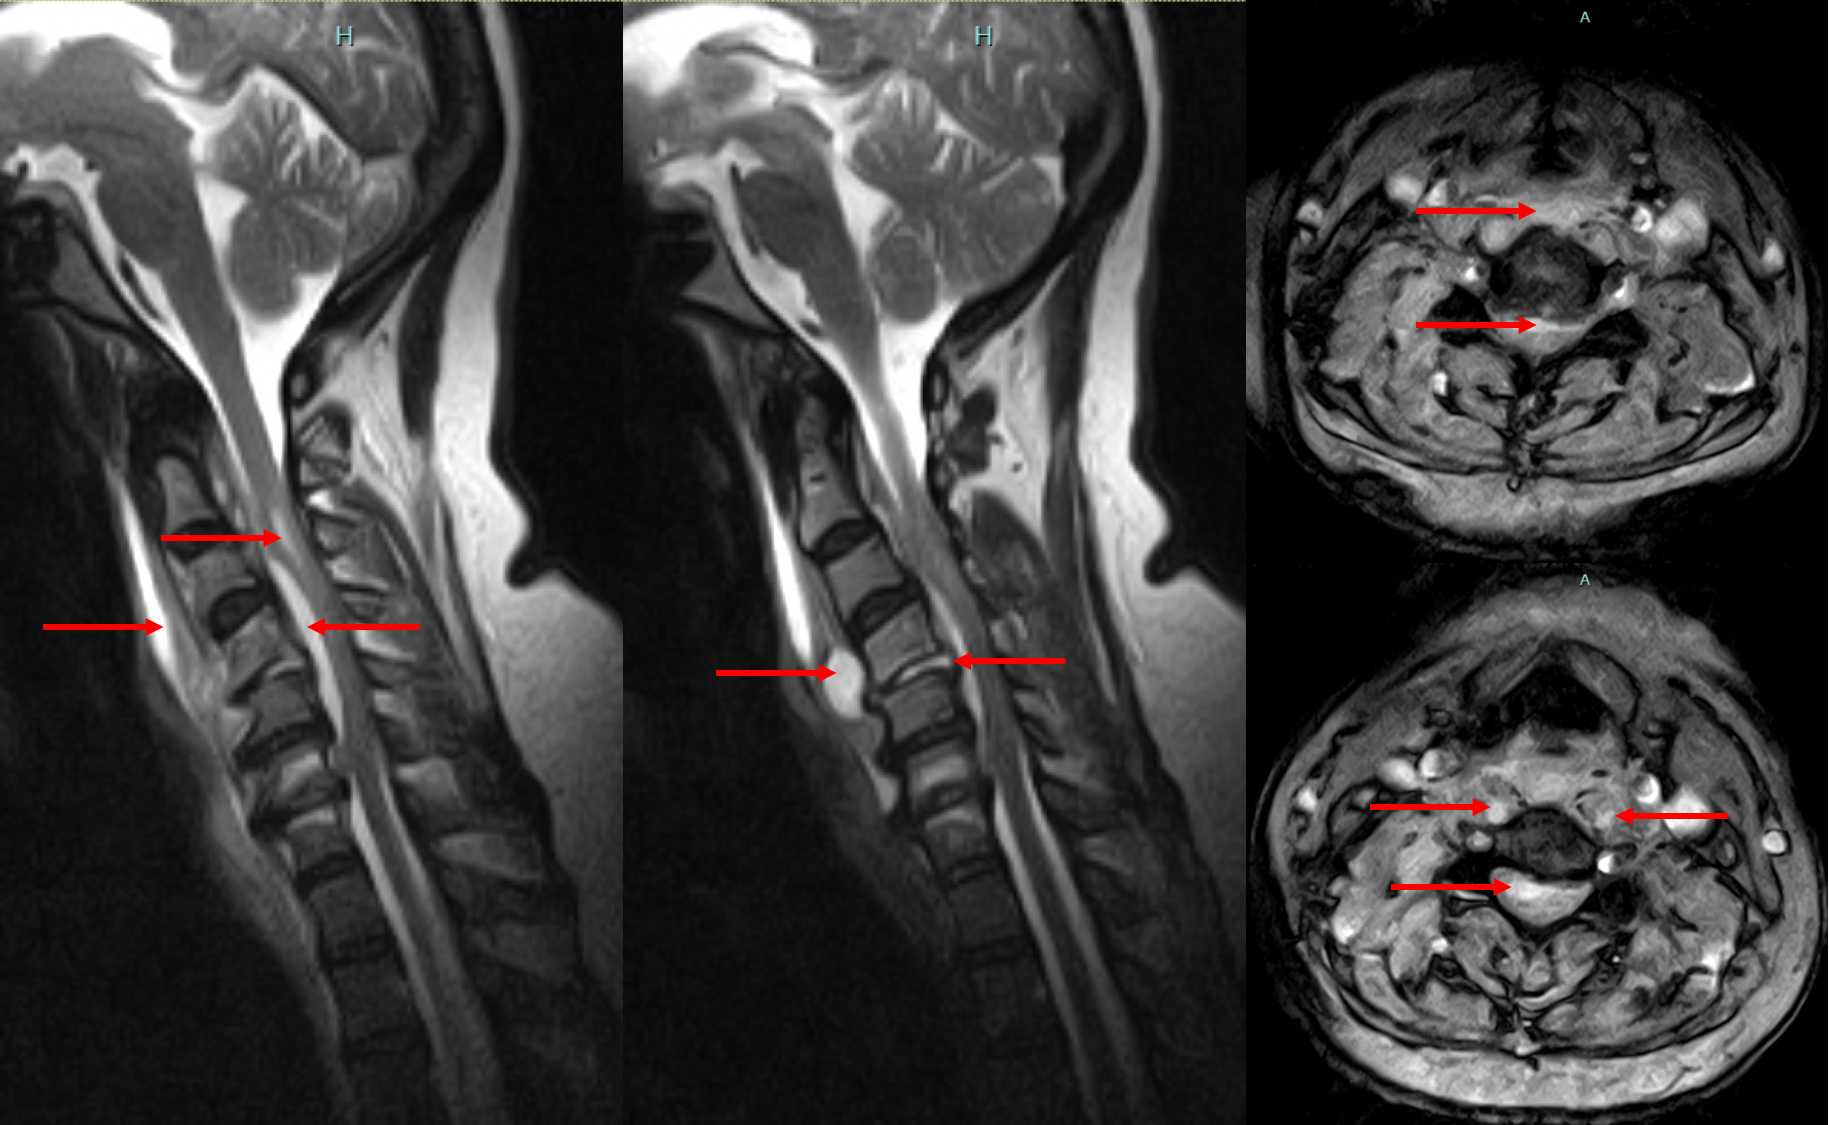

Neck Pain / Cervical Spondylosis

Chronic stiffness, limited movement, nerve compression, radiating pain.